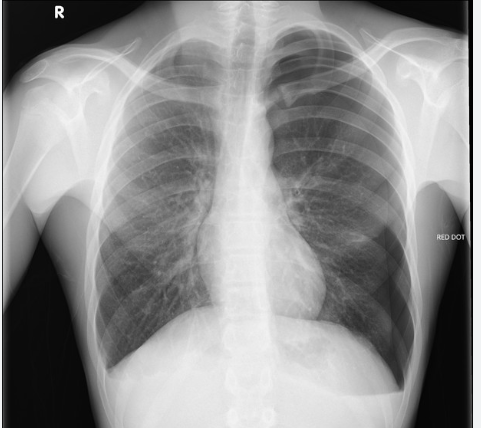

This CXR causes hypoxia due to which underlying mechanism

V/Q mismatch